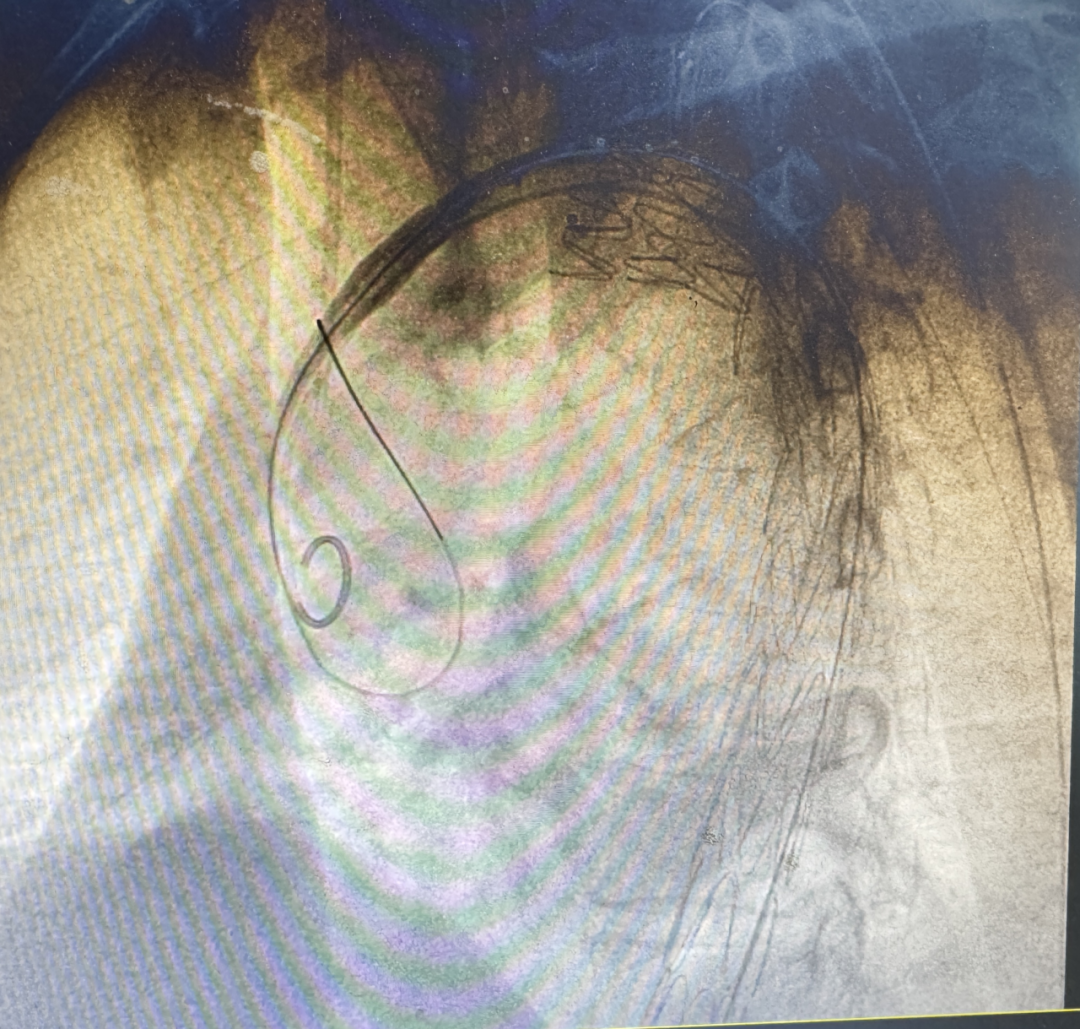

深夜23:15,救护车尖锐的鸣笛划破金华夜空——一场与死神赛跑的生死竞速,在金华市中医医院创伤中心悄然上演。患者方先生因严重车祸被紧急送入急诊科时,血压已跌至60/40mmHg,相当于正常人的“半血条”,随时可能心脏骤停。

“三段式”手术

堪比精密拆弹